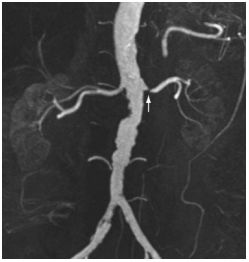

65. 28歲女性因8週的下腹絞痛合併腹瀉病史,接受進一步評估,她每天排便6至10次,其中有一至二次在半 夜,大便特徵為loose to watery with intermittent blood streaking。另外她有噁心及食慾變差現象,但無嘔 吐、發燒,也無服用藥物病史。身體檢查:體溫:37.8℃,血壓100/54 mmHg、脈搏96/min,腹部呈 現diffuse tenderness但無rigidity, guarding或rebound pain。大腸鏡檢查在升結腸、橫結腸及降結腸有如 附圖之發炎病灶,但是terminal ileum及rectum並無發炎現象,下列何者為最可能之診斷?

(A) Collagenous colitis (B) Crohn colitis (C) Ischemic colitis (D) Ulcerative colitis (E) Tuberculous colitis